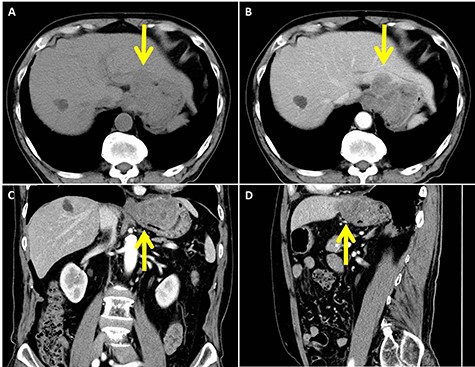

In abdominal enhanced computed tomography, a slightly low-density tumor of about 70 mm in diameter at the cardia (arrow) was seen. It appeared to infiltrate into the liver directly. (A: plane; B: axial image in the artery phase; C: coronal image in the artery phase; D: sagittal image in the artery phase)

On investigating, his hemoglobin was 10 g/dl, and tumor markers, carcinoembryonic antigen and carbohydrate antigen 19-9 (CA 19-9), were elevated to 12.5 ng/ml and 94.3 U/ml, respectively. Tests for Hepatitis B and C viruses were negative. His upper GI endoscopy showed SMT with delle at the lesser curvature of the cardia (Fig. 1). A computed tomography (CT) showed a slightly low-density tumor of 70 mm in diameter at the cardia (Fig. 2). It appeared to infiltrate into the liver directly. We diagnosed it as gastric SMT (suspected GI stromal tumor) with liver infiltration.